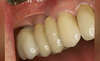

Vue au début du traitement, la patiente consulte pour des raisons esthétiques et fonctionnelles

Prothèses en place

Prothèse en 16

Prothèses en 24, 25, 26